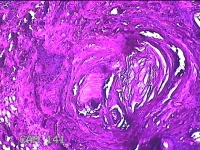

性别

男

年龄

47岁

临床诊断

皮脂腺囊肿

发现下颌部包块3年余,无疼痛及不适。

下颌部包块

大体所见

灰白暗红色带皮肤结节1.5x1.3x0.8cm一个,表面糜烂,切开结节呈实性,切面灰白粉红色,质软。

图1